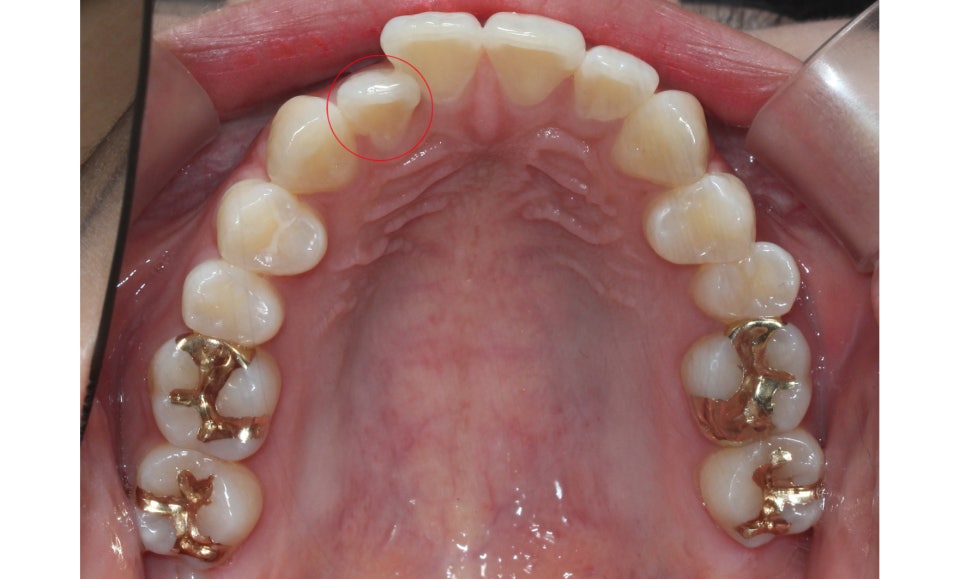

좌우의 교합평면을 보면 구치부의 교합은

크게 틀어진 부분 없이 양호한 상태인데요,

상악의 경우 송곳니의 위치나 각도도

좋기 때문에 부분교정도 가능하나

전체적인 교합을 바르게 하기 위해

자가결찰브라켓인 클리피씨교정 장치를

적용하여 전체교정을 진행하였습니다.

상악의 경우 설측으로 뻐드러져 있는

측절치의 바른 교정이 중요한 포인트이기 때문에

이를 중심으로 교정 계획을 수립하였습니다.

또한 미세하게 발견되고 있는 crowding으로 인해

삐뚤어진 정중선 역시 바른 각도로 교정하도록 하였습니다.